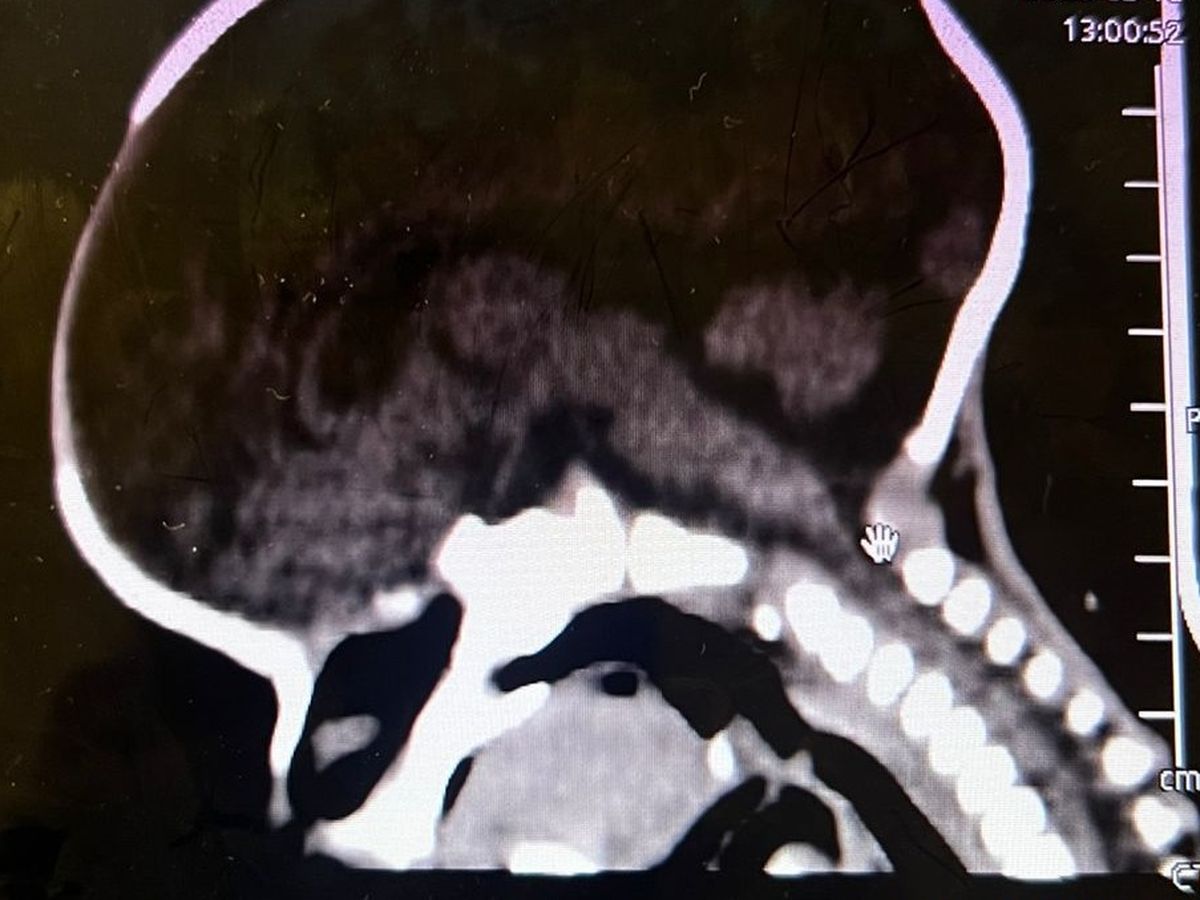

Hola mi nombre es Diana y hace aproximadamente un mes nació mi sobrino Santiago, ayer le acaban de detectar craneosinostosis y es necesario realizarle una cirugía en su cabecita lo más rápido posible para que su cerebro pueda tener un desarrollo adecuado, para realizar esta cirugía en los hospitales públicos hay lista de espera de seis meses aproximadamente y debido a la urgencia y que vamos contra reloj ya que se debe realizar en los primeros meses de vida que es cuando es menos riesgosa la operación por eso la única opción que nos queda es realizarla en un hospital privado por eso el costo tan elevado, les pido de todo corazón su ayuda cualquier aportación es de gran ayuda para poder juntar el dinero cuanto antes y el pequeño Santi pueda ser operado cuanto antes.